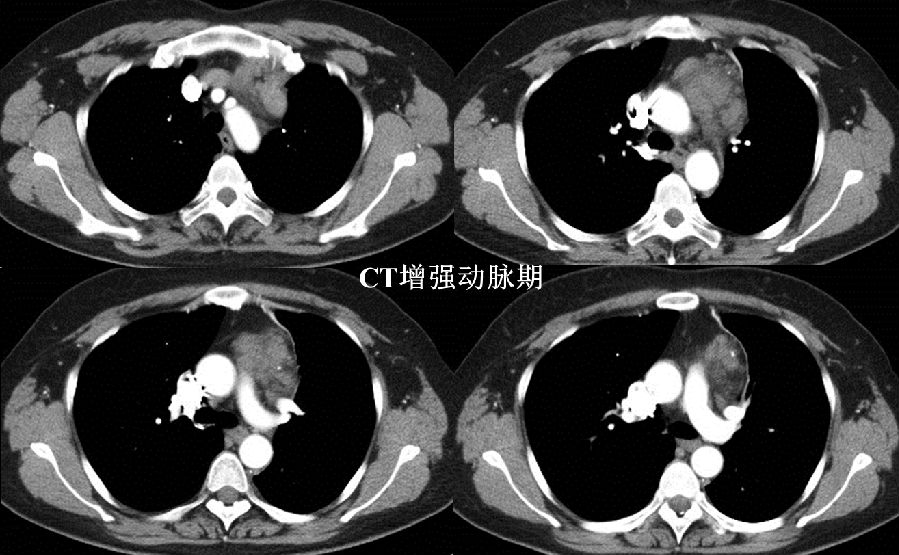

病例提供 伍建林教授(大连大学附属中山医院) 简要病史 患者,女,45岁 主诉:胸前区疼痛、胸闷3年,加重半月余。 现病史:3年前患者无明显诱因出现间断性胸前区疼痛、胸闷,伴后背部疼痛,运动后上述症状加重,无呼吸困难,无头晕、头痛,于当地医院行冠脉造影示:冠状动脉粥样硬化,具体治疗不详,出院后自服硝酸甘油,上诉症状可缓解。半月前,患者上诉症状加重,于当地医院行胸部CT检查发现:左前上纵隔肿物,并于我院门诊以“纵隔肿物”收入院进一步诊治。病来无咀嚼无力,无气短,无咯血,无关节疼痛,无进行性消瘦,无恶心、呕吐、低热盗汗等。 既往史:胸背部脂肪瘤术后8年;高血压病史4年,自服药物治疗效果良好;否认其他病史。 一般查体与专科查体无明显异常。 影像资料